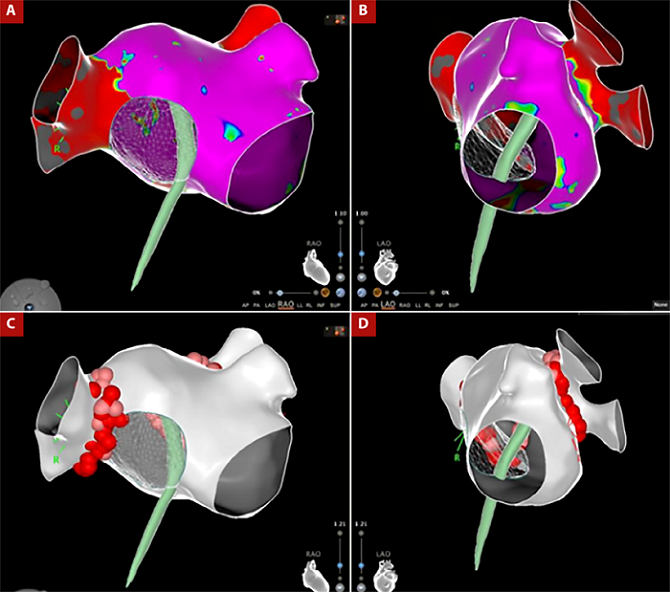

Debido a la no progresión de la vaina sobre el septum interatrial remanente, fue necesario intercambiar la aguja de punción transeptal con una guía 0,035” pasándola hacia las venas pulmonares izquierdas y con este soporte avanzamos el introductor largo hacia la aurícula izquierda. Debido a la dificultad del abordaje decidimos realizar el procedimiento con solo una punción transeptal. Pasamos el catéter de mapeo de alta densidad PENTARAY (Biosense - Webster, Diamond Bar, California) para realizar la reconstrucción anatómica tridimensional de la aurícula izquierda y las cuatro venas pulmonares (VPs), seguido del paso del catéter de ablación curva D con sensor de fuerza de contacto THERMOCOOL SMART TOUCH - SF NAV (Biosense - Webster, Diamond Bar, California), con lo que realizamos el aislamiento antral circunferencial de las cuatro VPs, aplicamos radiofrecuencia punto a punto empleando el software VISITAG SURPOINT (Biosense - Webster, Diamond Bar, California) alcanzado un índice de ablación de 400 en pared posterior y 550 en pared anterior (Figura 3). Se realizó la verificación de la actividad eléctrica de las Vps izquierdas y derechas observando un bloqueo bidireccional, las maniobras de sobreestimulación no indujeron taquiarritmias atriales. Finalmente, retiramos el catéter de ablación hacia la aurícula derecha y realizamos una línea de ablación en el istmo cavo tricúspideo, alcanzado bloqueo bidireccional de esta zona. El paciente fue dado de alta, con terapia antiarrítmica (propafenona 150 mg tres veces por día y bisoprolol 5 mg una vez al dia) y anticoagulación con warfarina, sin presentar complicaciones agudas ni recurrencias a los 6 meses del seguimiento clínico.

Figura 3 A-B. Reconstrucción 3D de la aurícula izquierda con mapa de voltaje, el cual muestra zonas de bajo voltaje en las venas pulmonares izquierdas que expresan aislamiento eléctrico. C-D Reconstrucción anatómica 3D de aurícula izquierda con imagen de la punción transeptal, donde se observan los puntos de ablación por radiofrecuencia en la región antral circunferencial de las cuatro venas pulmonares.